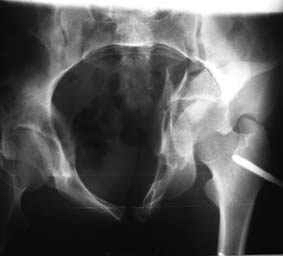

Все-таки надо бы начать не с КТ, а с обзорного снимка таза и косых проекций впадины.

Это обзорные и косые снимки

С уважением,

Привет, Леонид. Оскольчатый высокий двухколонный перелом в такие сроки трогать не надо, т.к. это про такие переломы сказано: "кто с ножом на Ж. пойдет тот в ней и останется...".